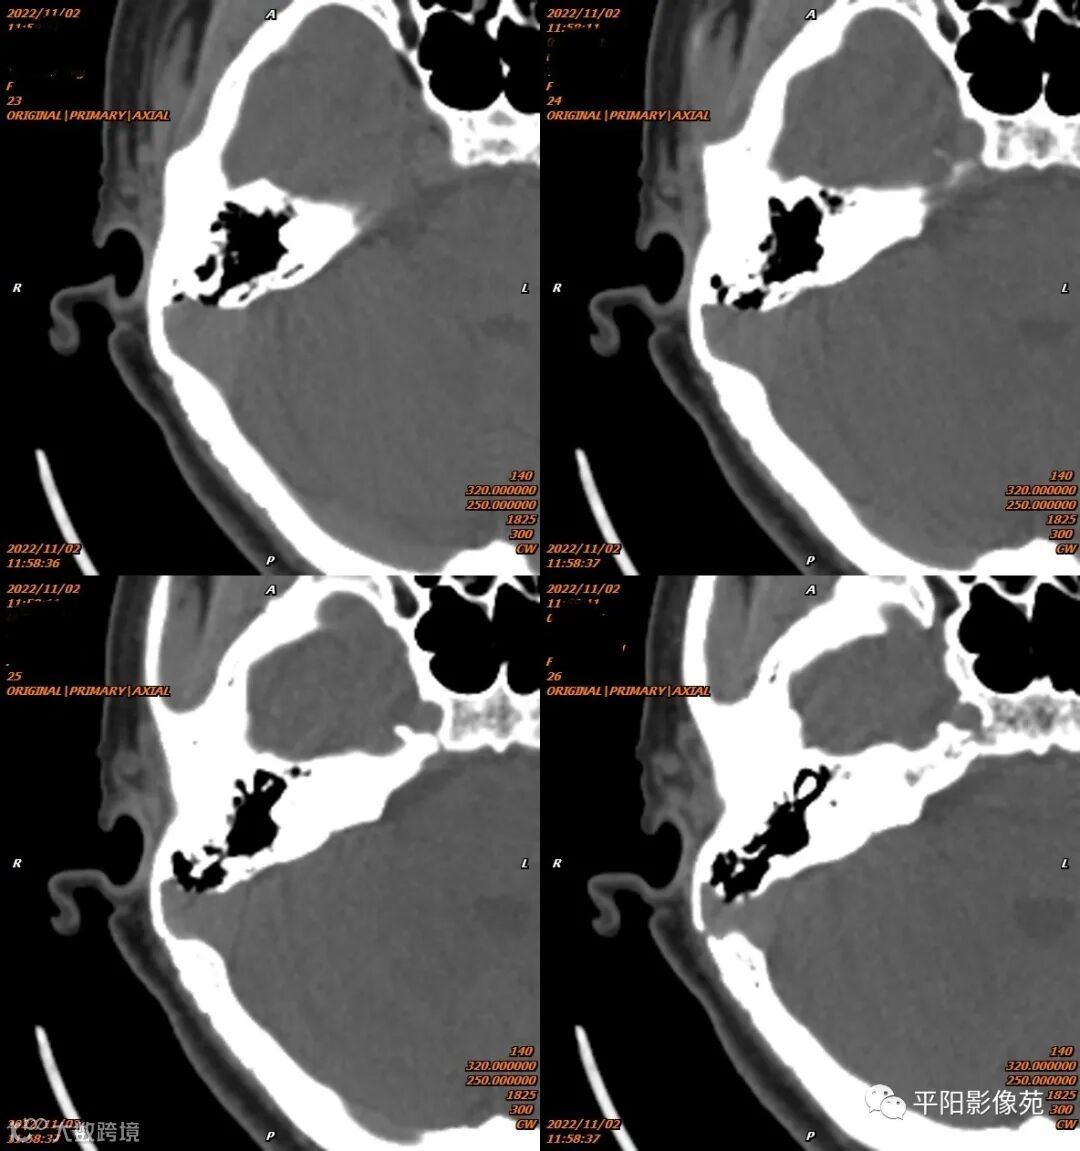

影像表现

影像表现:乙状窦局限性扩大,向右侧膨出,压迫右侧颞骨凹陷,前方乳突气房骨壁缺损。

影像诊断:乙状窦憩室